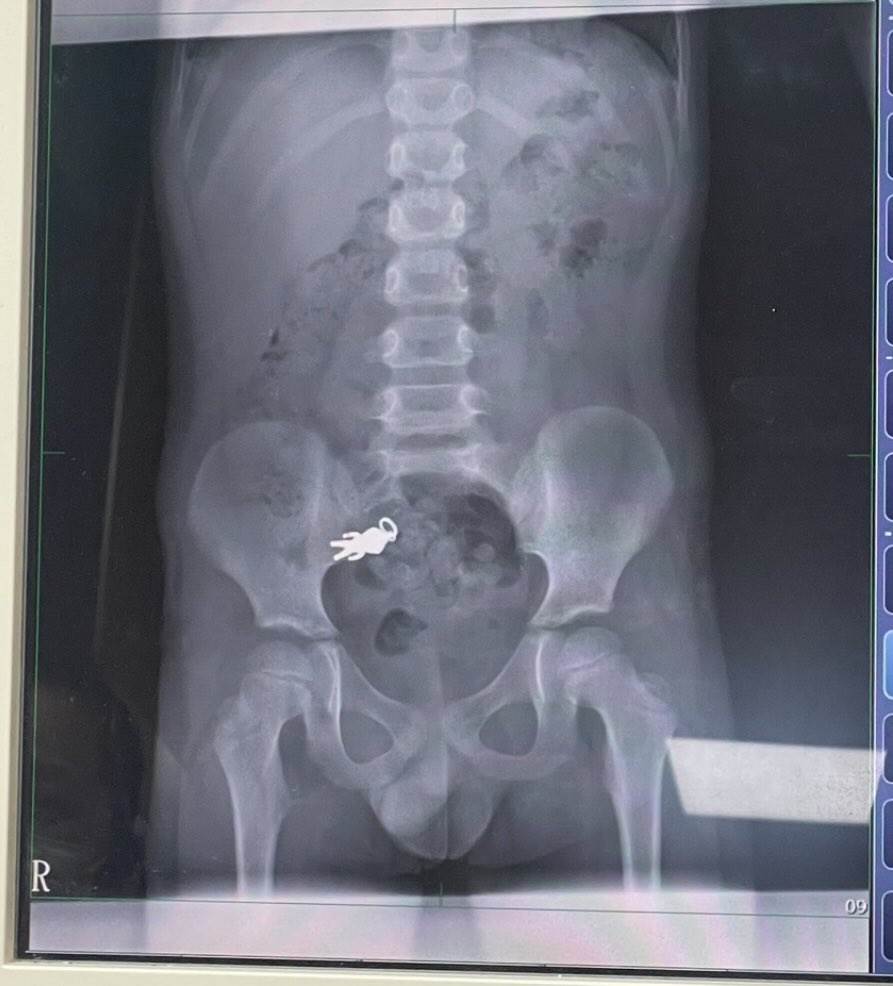

宜蘭一名7歲男童日前在家中一邊追劇一邊品嚐零食時,竟不慎將隨身攜帶的奧特曼吊飾誤食入腹,讓家人驚慌失措,立刻帶他趕往羅東博愛醫院就醫。

仔細一看X光片,還能看到奧特曼的完整形狀,意外在網路上引發討論。

根據《CTWANT》、《ETtoday新聞雲》報導,男童的家屬在threads貼出照片,只見畫面中男童的腹腔內,清晰可見一個異物的輪廓,形狀與大小都與奧特曼吊飾完全吻合。主治醫師謝錦桐表示,這枚吊飾的尺寸約為2.8公分乘1.4公分,目前已順著腸道蠕動進入小腸區域。

所幸經過詳細檢查,男童的生命徵象相當穩定,也沒有出現任何不適癥狀。醫師建議家屬不需立即採取開刀或侵入性治療,只要持續觀察男童的排便情況,等待吊飾自然排出即可。

後續家屬也在網路上分享好消息,表示男童已經順利將奧特曼吊飾排出體外,還特地將吊飾清洗乾淨。網友看到圓滿結局都鬆了一口氣,紛紛留言「恭喜奧特曼重獲新生」、「這趟體內之旅總算完美落幕」。醫師也藉此提醒家長,孩童進食時應該避免邊吃邊玩,以預防類似意外發生。